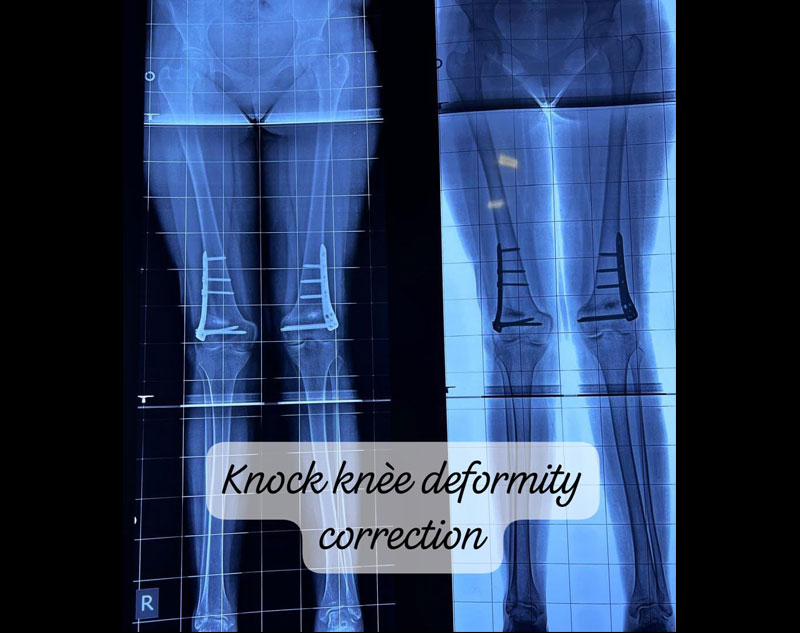

Knock knees are a condition where the knees angle inward, causing them to touch while the ankles remain apart. This misalignment can cause abnormal walking patterns, joint pain, and even arthritis over time.